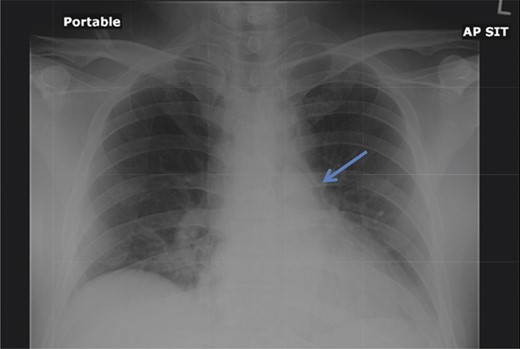

A 42-year-old male with a past medical history of hypertension was admitted for an elective TEP repair of his left inguinal hernia. Endotracheal intubation and general anesthesia were given uneventfully. The extraperitoneal space was developed with a balloon space maker, and insufflation of carbon dioxide at a maximum pressure of 12 mmHg was performed. Intraoperatively, a large incarcerated indirect left inguinal hernia containing omentum was reduced. A Optilene mesh (10 × 12 cm) was placed and tacked appropriately after hernia reduction. There were no obvious tears in the peritoneum and the total operative time was ∼90 min. No elevation of end-tidal CO2 was noted during the surgery and the patient was extubated successfully. The patient subsequently complained of left-sided chest pain on the same night of the surgery. He did not have abdominal pain. He had subcutaneous crepitus extending from the left groin to the left chest. His cardiac enzymes were negative and his electrocardiography revealed a sinus rhythm with no acute ischemic changes. A plain radiograph of the chest showed a sliver of lucency in the mediastinum suspicious for pneumomediastinum, with no obvious pneumoperitoneum or pneumothorax seen (Fig. 1). Computed tomographic (CT) imaging of the thorax and abdomen confirmed the radiograph finding of pneumomediastinum and diffuse subcutaneous emphysema tracking along the abdominal muscles bilaterally, as well as a small amount of free air and stranding in the left posterior pararenal space (Figs 2–4). The patient was treated conservatively with oral analgesia and supplemental oxygen. His chest pain resolved by the third postoperative day and he was discharged well. He was advised to avoid air travel for 1 month. He was reviewed in clinic at the 1-week and 1-month intervals and did not report any further chest pain or respiratory symptoms. His operation site healed well and he remained recurrence free.

Chest radiograph demonstrates a pneumomediastinum (arrowhead).